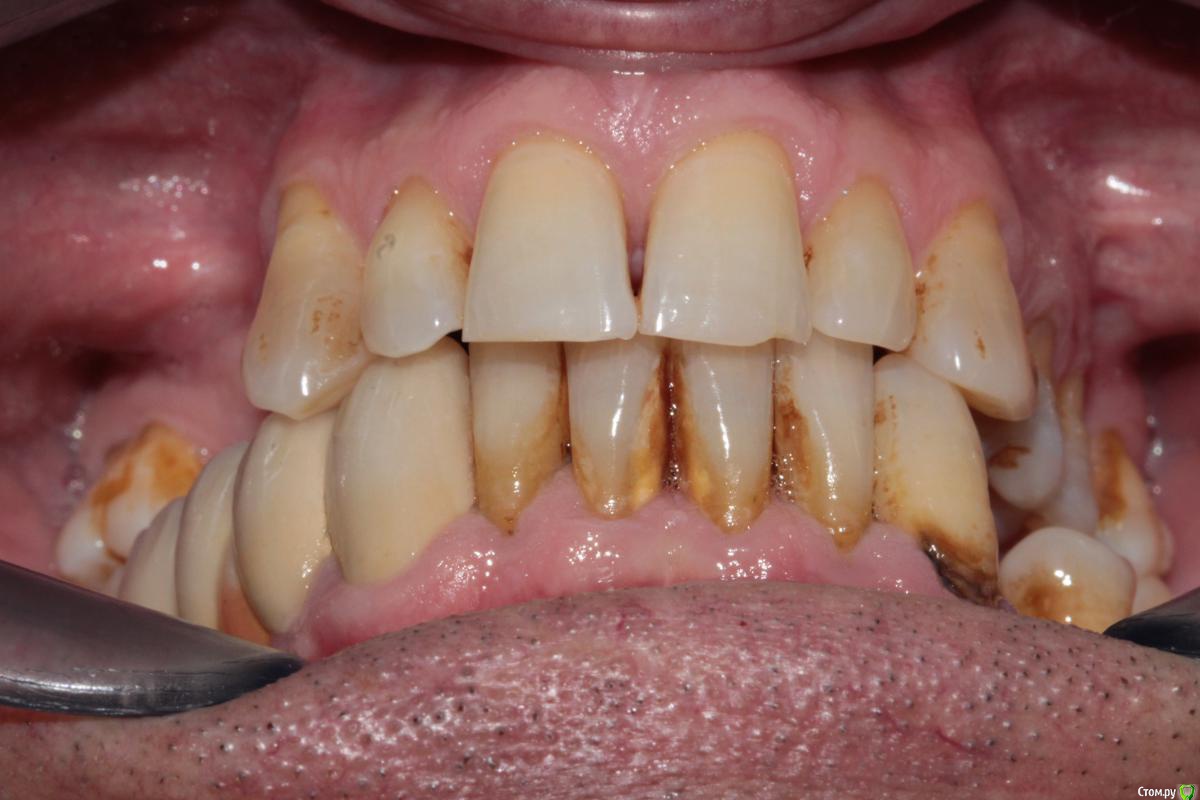

Меня больше смущает 2 момента, 1й - это то что на верхней челюсти зубы "разбросаны" как попало, не знаю что можно сделать не собрав их вместе предварительно. 2ой - в 4ом сегменте мост, консольный, его снимать не хочется, так как его по сути недавно поставили, а не сняв его не знаю что можно сделать в 3ем сегменте, если имплантацию откидываем как вариант....

Был предложен вариант сделать бюгель, с обычными кламмерами на верхней челюсти, как думаете при таком расположении зубов, это правильно?

P.S. - не совсем понятно как получилось  так, что фронт в контакте а премоляры вне контакта (слева).

спасибо за ответ. Я с вами полностью согласен, хороший план, но меня вот беспокоят два момента: 1й - на верхнюю челюсть если сделать бюгель с кламмерами, то в области 24,25 там маленький зазор, а между 25 и 27 там зазор такой, что зуб вроде бы не поместится, в таких случаях там зуб не ставить? просто каркас?

2й момент - слева премоляры вне контакта, если работать под существующий прикус (скорее всего так и будем работать) то они опять останутся без контакта, это не будет проблемой?

Поместится,в крайнем случае чуть пришлифуйте апроксималку,а зазор между 24 25 я думаю пациента не беспокоит,если беспокоит,пожалуйста,делайте дополнительно коронки и решайте вопрос.а по поводу низа если мост будет 33-35 то вы доведете их в контакт окклюзионно и пространства там не будет